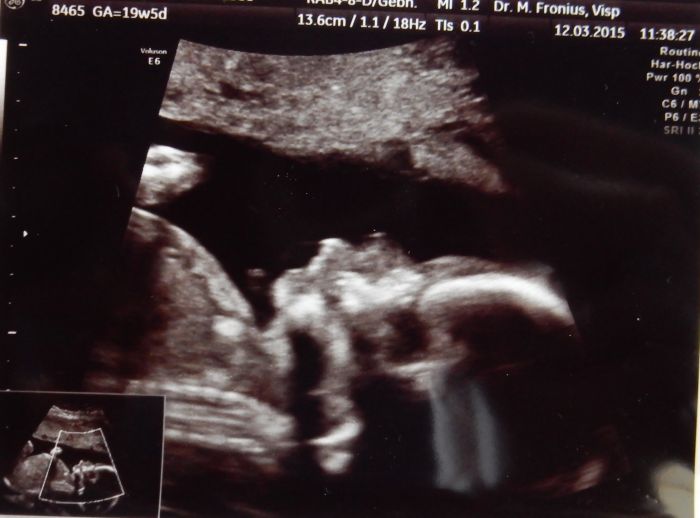

Ahoj holky, tak hlásím prohlídku ve 21tt. Termín nám zůstává stále na 1.8., prcek váží 340g a má se čile k světu. Krásně si skoro celou dobu cucal palec a prý máme fotogenické dítě :-) Tlak opět trošku vyšší, doufám, že se to nebudu zhoršovat. Zatím jsem ještě v toleranci, ale... No a váha... přemýšlím, kde jsou ta kg, mám nahoře kolem 4,5kg. Ani bych to neřekla. Jinak máme vše v naprostém pořádku. A dneska jsem si to konečně užila tu prohlídku. Bylo to super. Dostali jsme další průkazku, kdyby jsme náhodou rodili tady. No a pokud ano, tak se prý musíme ve 30tt nahlásit v porodnici tady v nemocnici. Takže opravdu nevíme jak to provedeme. A co čekáme už taky víme

Tak jsme koupili ještě dvoje kalhoty a dvoje pidi ponožky, ať má to malý radost. Máme asi 8 fotek, tak aspoň dvě přikládám. Za chvíli se půjdu natáhnout a v posteli vás dočtu. Mám jen přidat trošku hořčíku, čím víc tím líp.